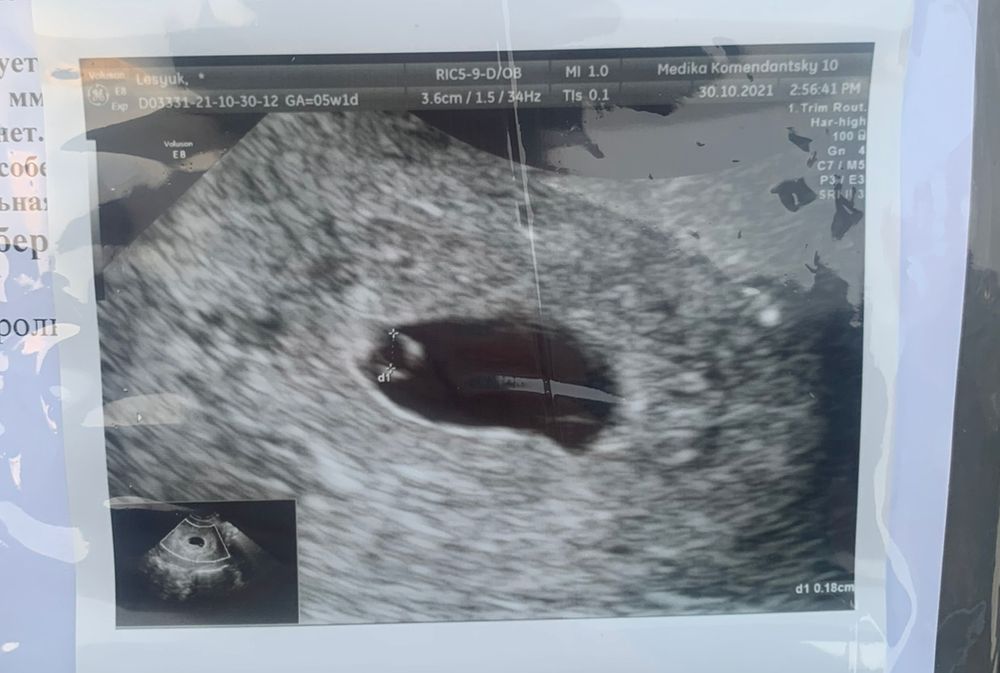

На вашем снимке качество не очень. Вот вам для сравнения белая точечка это эмбрион, ктр тут 2,4 мм, а прозрачный кружок рядом, это жм Изображение